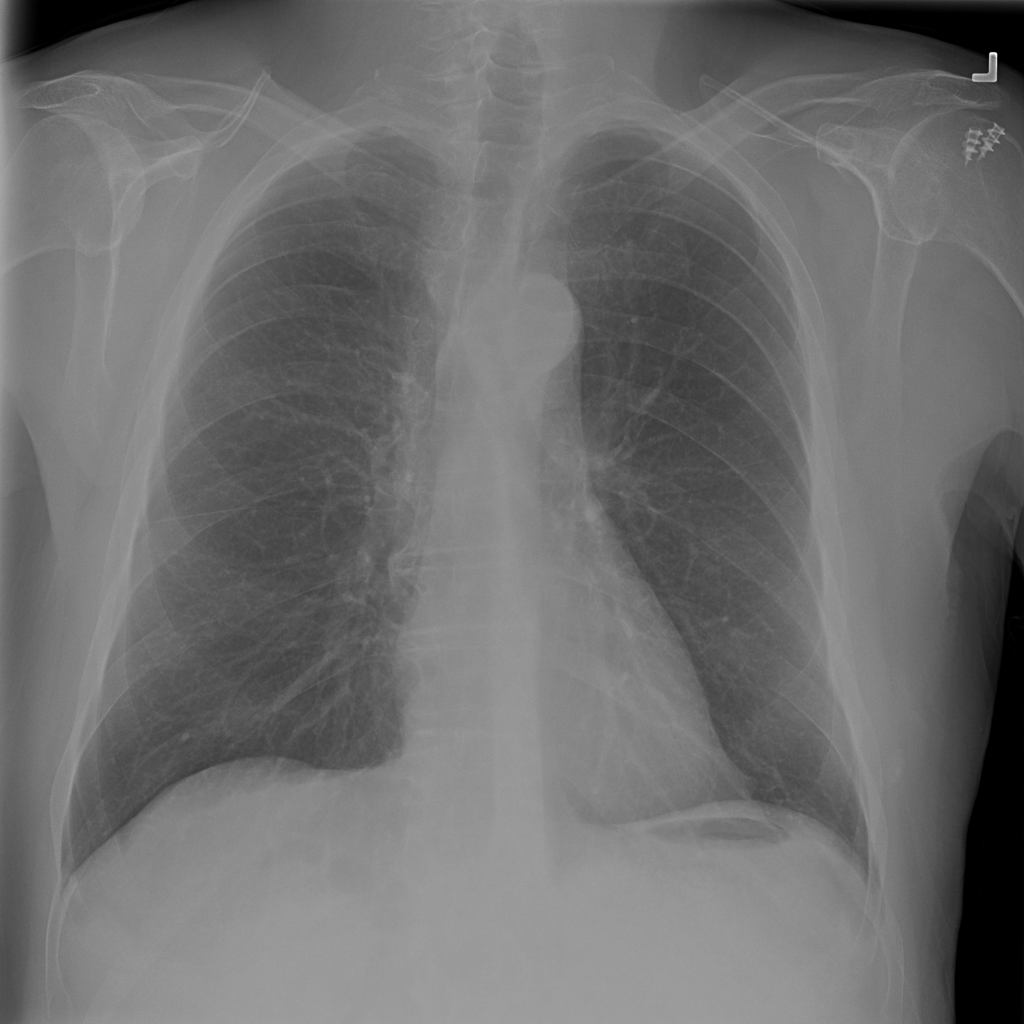

PAT-894B · IMG-000Emphysema

PAT-894B · IMG-000

PA